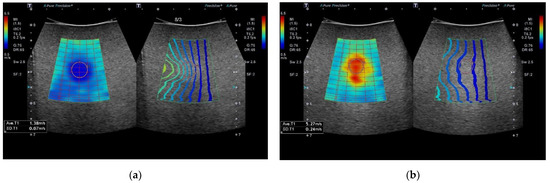

Modern 2D-SWE systems now incorporate software tools to assist operators to visually assess the stability of the acquired SWV and to inform them of the ideal placement of the sampling region of interest (ROI) box [21]. Alongside a 2D colour-coded map of tissue stiffness, a novel approach provided by some manufacturers is the addition of a “propagation contour map” (Figure 1), which uses a series of contour lines to depict shear wave arrival times at different anatomical points in the tissue being assessed [22,23]. Regions in the image displaying parallel contour lines indicate shear waves are propagating smoothly with minimum variability [21]. These two images provide complementary information designed to produce a visual indicator of the best acquisitions to select for quantitative analysis and to optimise the placement of the ROI sampling box in an area free of significant artefacts. Operators utilising 2D-SWE technology need to have confidence that any derived measurements are a true representation of the tissue being sampled and have a good understanding of the factors that can introduce variability. Thus allowing them to take steps to minimise these at the time of imaging.

Figure 1.

2D-SWE Ultrasound elastography display of two phantom targets using circular ROI (a) Type IV (85 kPa) and (b) Type I (10 kPa). Each image display is split into the parametric colour map on the left, (higher SWV coded as red/orange and slower SWV as blue/green) and reliability propagation map on the right (parallel lines indicating increased reliability).

The intervals between the contours on the visual propagation map are wider in regions where the shear waves travel faster and closer together when travelling slower (Figure 1). Areas of parallel contour lines represent areas in which shear waves propagate smoothly and indicate that the reliability of data acquisition in these areas is highest [8].